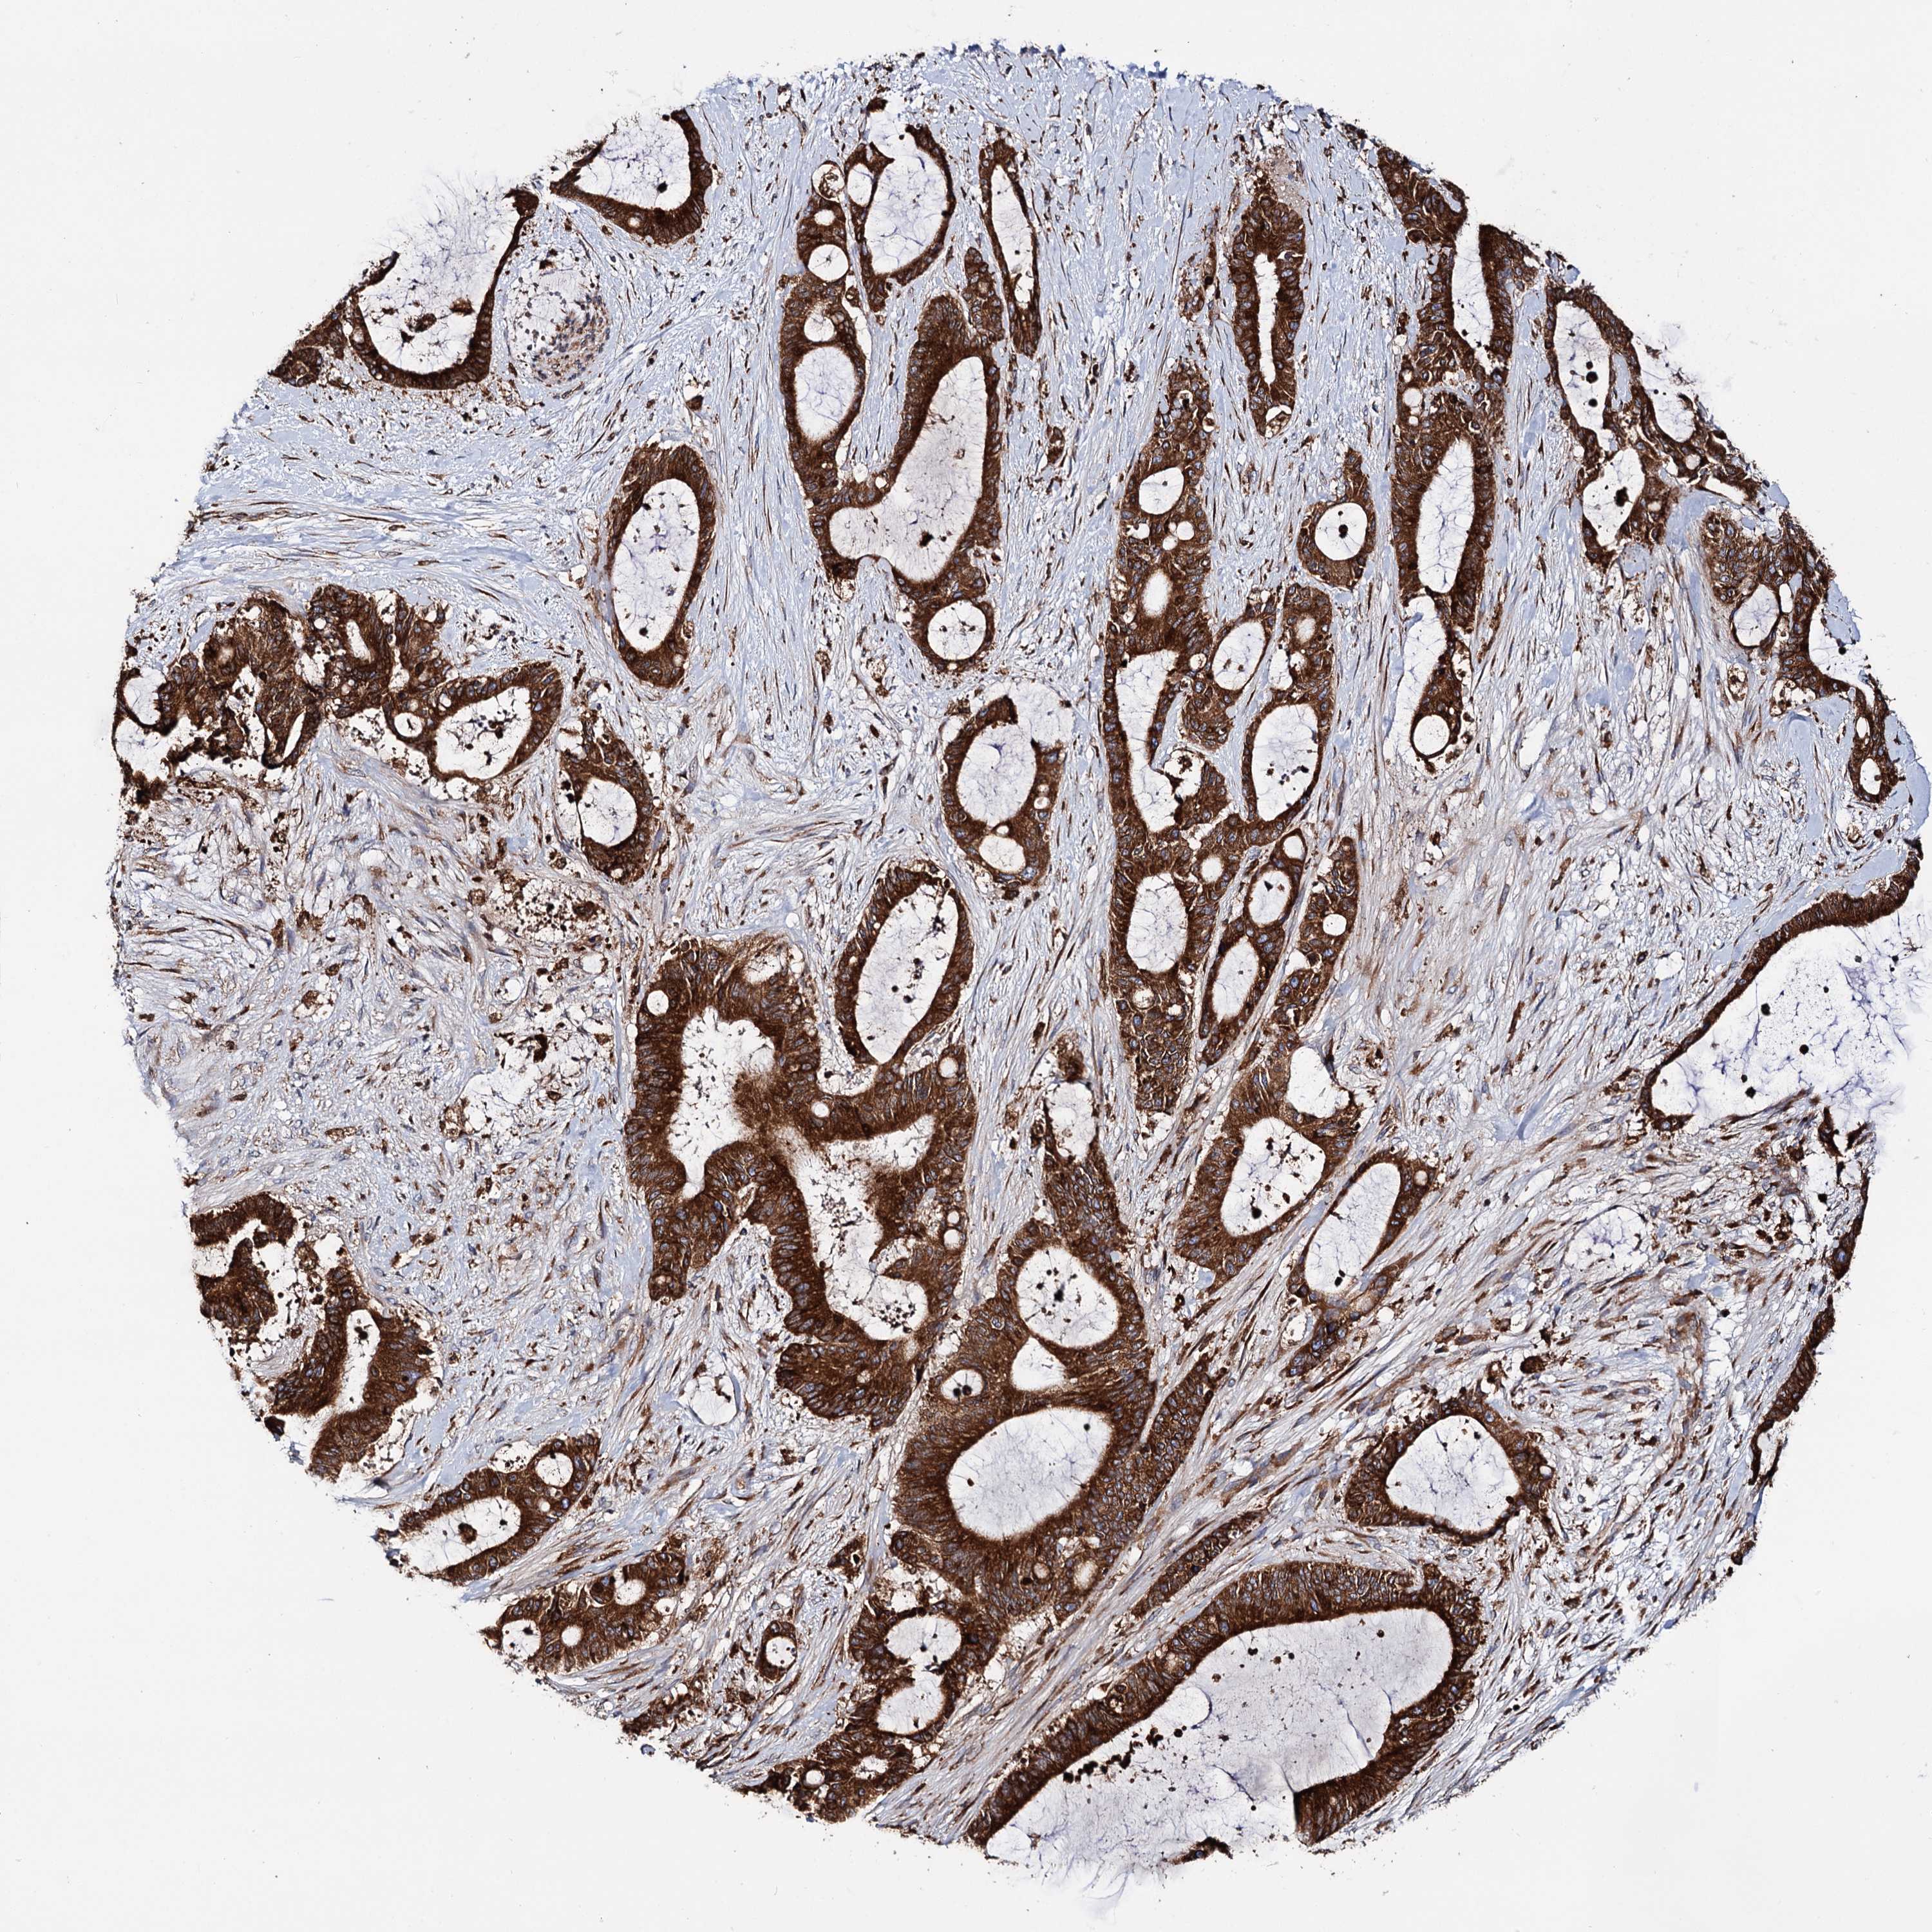

LIVER CANCER - Protein expressioni

A mouse-over function shows sample information and annotation data. Click on an image to view it in a full screen mode. Samples can be filtered based on level of antibody staining by selecting one or several of the following categories: high, medium, low and not detected. The assay and annotation is described here.

Note that samples used for immunohistochemistry by the Human Protein Atlas do not correspond to samples in the TCGA dataset.

Antibody stainingi

Antibody staining in the annotated cell types in the current human tissue is reported as not detected, low, medium, or high, based on conventional immunohistochemistry profiling in selected tissues. This score is based on the combination of the staining intensity and fraction of stained cells.

Each image is clickable and will lead to virtual microscopy that enables deeper exploration of all samples and also displays staining intensity scores, fraction scores and subcellular localization as well as patient and tissue information for each sample.

Antibody HPA039363

Antibody HPA039456

Staining

High

Medium

Low

Not detected

Intensity

Strong

Moderate

Weak

Negative

Quantity

>75%

75%-25%

<25%

None

Location

Nuclear

Cytoplasmic/membranous

Cytoplasmic/membranous,nuclear

Cholangiocarcinoma

Carcinoma, Hepatocellular, NOS